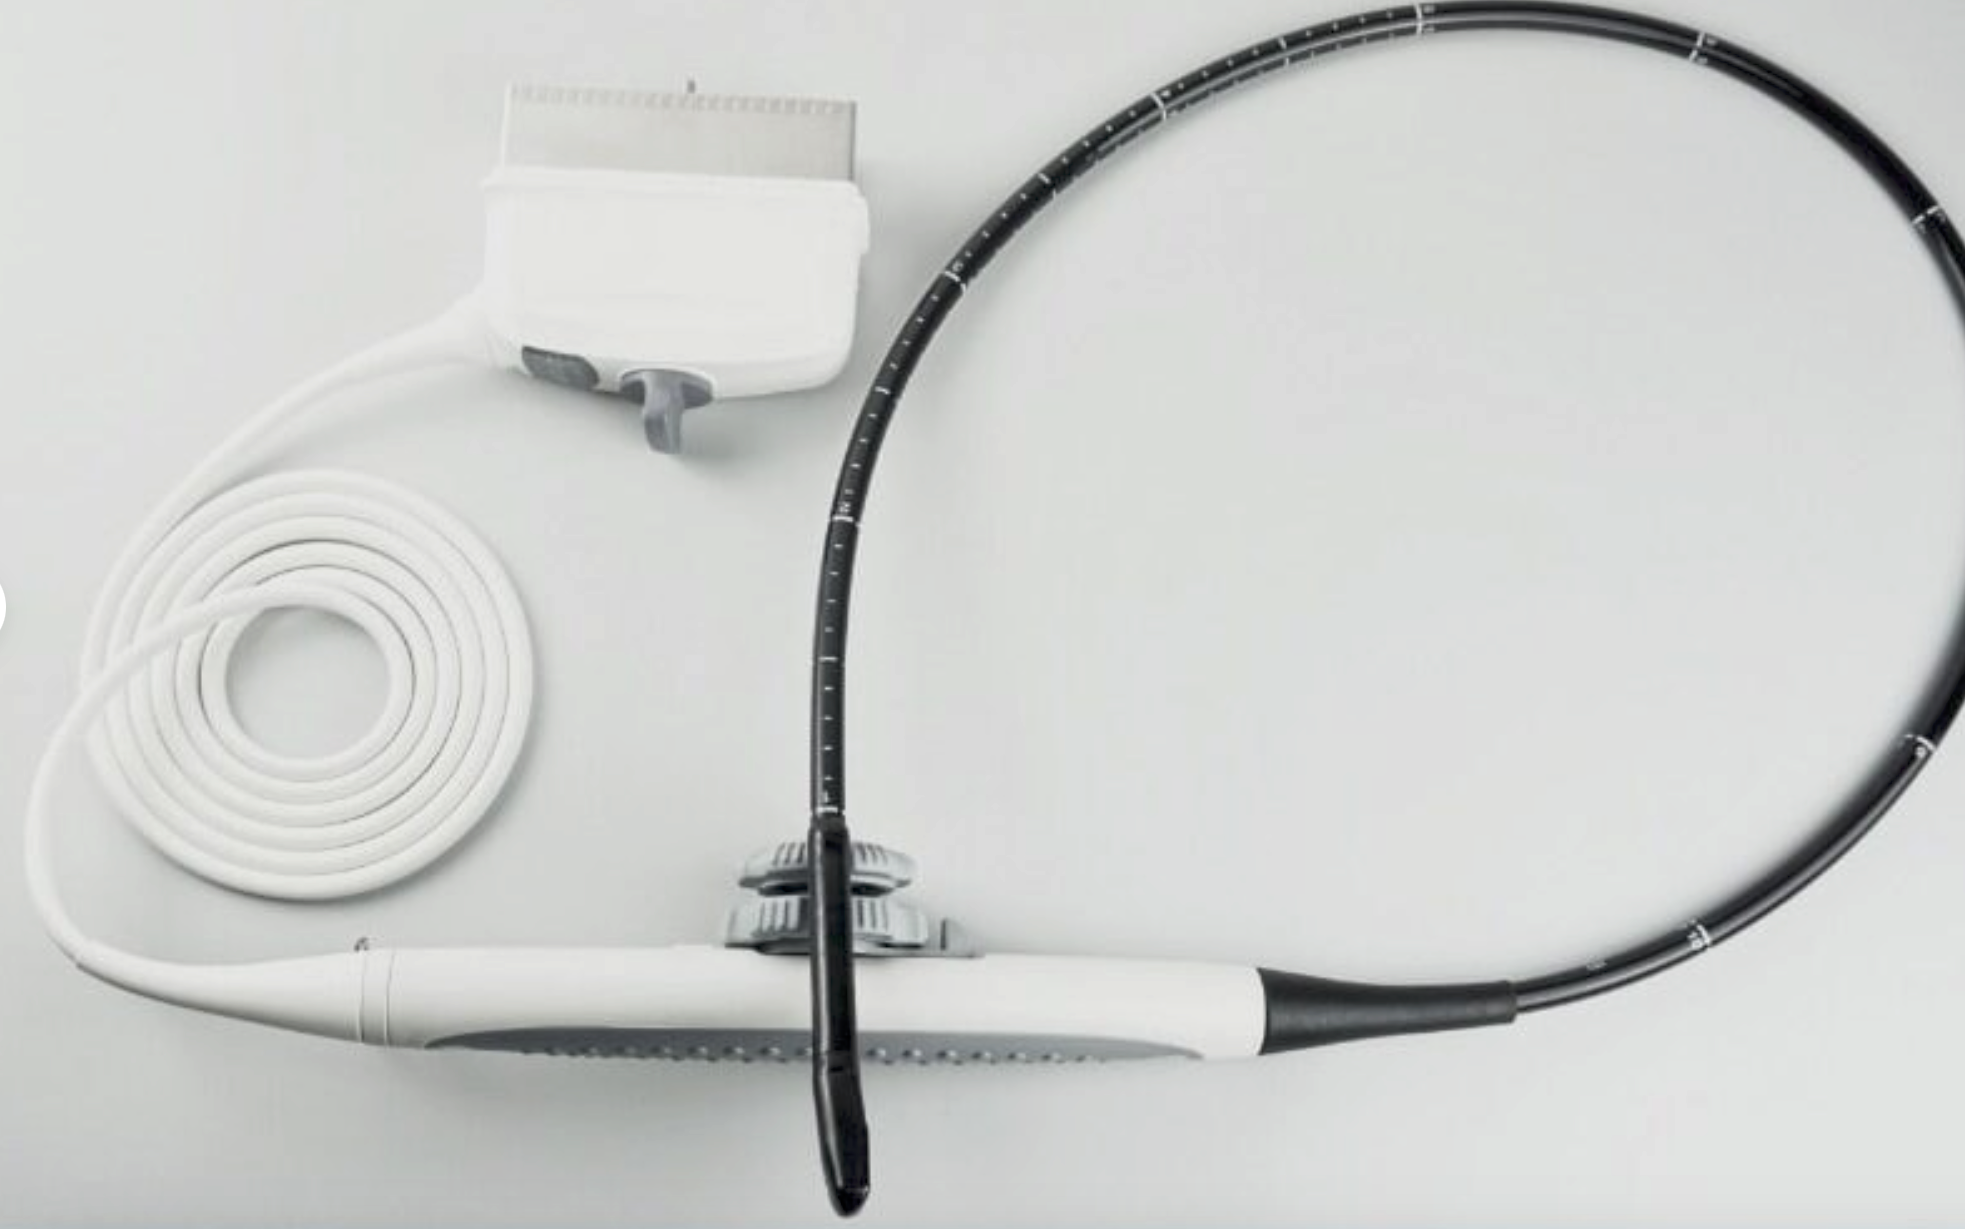

Seller Notes:âThe unit is in good cosmetic condition with some signs of wear and tear consistent with normal use (See Pictures). The unit was tested at our facility and found to be in good working order. Samsung Medison 3D 2-6ET 3D/4/D Convex Probe Bandwidth: 2 â 6 MHz Applications: Abdomen, Obstetrics, Obstetrics Early, Gynecology, Fetal Heart S/N: 275-K-A330Aâ